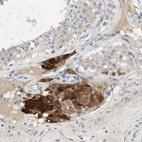

Immunohistochemical staining of human testis shows strong cytoplasmic positivity in Leydig cells.